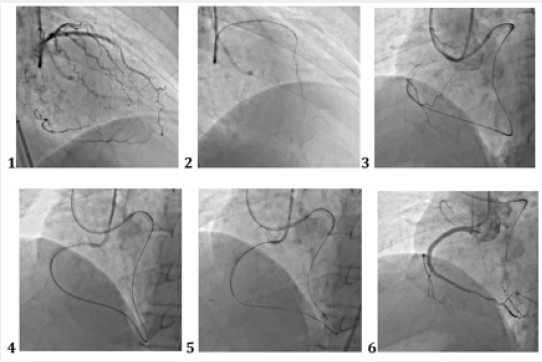

Figure 2: Reocclusion of PKA in a previously implanted stent. The technique of direct retrograde recanalization (direct retrograde crossing).

1. Visualization of the distal parts of the PCA through the system of septal collaterals. 2. Microcatheter “Corsair” allows selective filling of “interventional collaterals”. 3. Conductor and microcatheter in the distal parts of the PCA. 4. Successful conducting of the conductor through occlusion to the antegrade directional catheter. 5. Carrying out the microcatheter into the guide catheter, implementing the “trap” technique and manipulating “externalization”. 6. Stenting and final result.